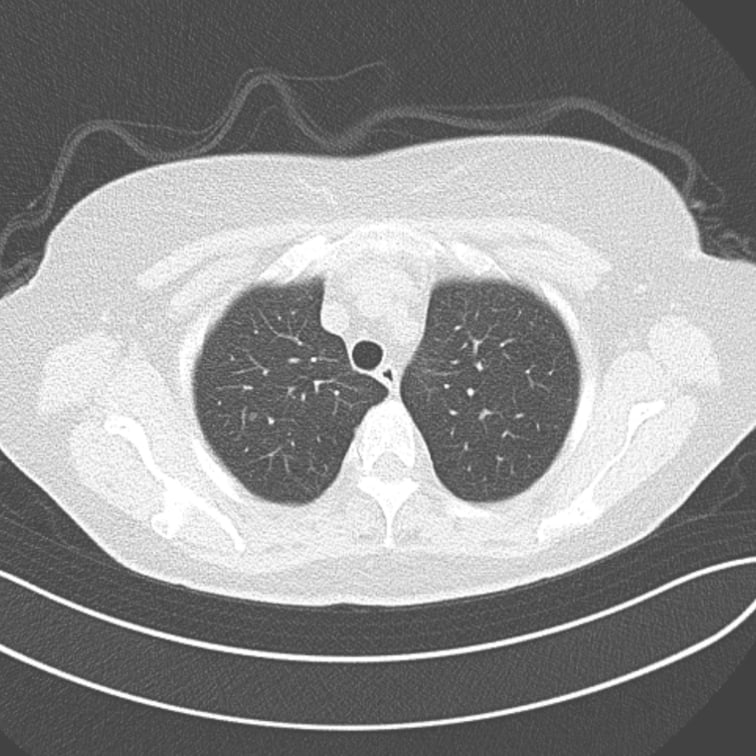

肺結節の候補領域を検出

読影枚数の多いCT画像診断において、

肺野領域の結節影の検出をサポート

- 肺結節候補領域検出

以下の肺結節候補領域を検出して表示します- 充実型:3mm以上30mm以下

- 部分充実型:5mm以上30mm以下

- すりガラス型:5mm以上30mm以下

標準線量CT